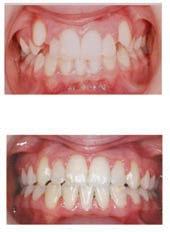

๊ฑด๊ฐํ ๋ฏธ์, ํดํผ์ค๋ง์ผ ์น๊ณผ์์

์ต์ ์ฅ๋น์ ์น์ ํ ์ง๋ฃ, ์ํ๋ํธ๊น์ง ๋ฏฟ๊ณ ๋งก๊ธฐ์ธ์!

ํนํ ํดํผ์ค๋ง์ผ ์น๊ณผ๋ ์ํ๋ํธ ์น๋ฃ

์ ๊ฐํ ์์ ๊ฐ์ ๊ฐ์ง๊ณ ์๋๋ฐ, ์์์

์น์ ๋ ์ฌ์ฉํ๋ ํ, ์ฆ ์น์์ ํฑ ๊ทผ์ก

์ ์ฌ์ฉํ์ฌ ์์์ ์๊ฒ ๋ถ์๋ ๋ฅ๋ ฅ๊ณผ

์ฌ๋ฏธ์ฑ์ ๋์์ ๋ง์กฑ์ํค๋ ์ํ๋ํธ๋

์์ฐ ์น์์ ๊ฐ์ฅ ๊ฐ๊น์ด ๋์ฒด ์น๋ฃ๋ก, ํ

๋์ ๋นํด ๋ ๋จ๋จํ๊ณ ์ค๋ ์ฌ์ฉํ ์ ์

์ธ์ ์น์๋ฅผ ๊น์ ํ์๊ฐ ์์ด ๊ตฌ๊ฐ ๊ฑด๊ฐ์ ์ ์งํ๋ ๋ฐ๋ ๋์์ด ๋๋ค. ํดํผ์ค๋ง์ผ ์น๊ณผ๋ ๋ณต์กํ ๊ตฌ๊ฐ์ธ๊ณผ ์์ ๊ณผ ์ง๋จ์ ์ํด ์น๊ณผ์ ์ฉ 3D CT ์ค์บ๋๋ฅผ ๊ฐ์ถ๊ณ ์์ผ๋ฉฐ, ์ด๋ฅผ ํตํด ์ ํํ๊ณ ์์ ํ ์ํ๋

ํธ ์์ ์ด ๊ฐ๋ฅํ๋ค. ํฑ๋ผ ์ํ, ์ ๊ฒฝ ์์น, ๋ผ์ ๋ฐ๋๊น์ง ์ ๋ฐํ๊ฒ ๋ถ

์ํ์ฌ ํ์ ๊ฐ๊ฐ์ธ์๊ฒ ์ต์ ํ๋ ์น๋ฃ ๊ณํ์ ์๋ฆฝํด๋๋ฆฐ๋ค.

๋ฟ๋ง ์๋๋ผ, ์ฌ๋ฏธ๋ณด์ฒ ๊ณผ ๋ฏธ์ฉ์น๋ฃ, ์ผ๋ฐ์น๊ณผ, ์์์น๊ณผ, ๊ตฌ๊ฐ์ธ๊ณผ, ์ ๊ฒฝ

์น๊ณผ ๋ฑ ๋ค์ํ ๋ถ์ผ์ ์ ๋ฌธ ์๋ฃ์ง์ด ํจ๊ปํด ํ ํ ์น๊ณผ ์ง๋ฃ๋ฅผ ์์คํฑ ์ผ๋ก ์ ๊ณตํ๊ณ ์๋ค.

ํดํผ์ค๋ง์ผ ์น๊ณผ์์๋ ์ ํธ๋(Aetna), ์ค์ฌ(Anthem), ํด๋ ๋ฒ์ผ์ด (Clever Care), ์์คํฐ๋ฐ(Astiva), ํด๋จธ๋(Humana), ๋ฆฌ๋ฒํฐ(Liberty), ์ ๋ ์ดํฐ๋ํฌ์ค์ผ์ด(United Healthcare) ๋ฑ. ๋ค์ํ ๋ณดํ์ ์ทจ๊ธํ๊ณ ์๊ณ , ๋ฉ๋์นผ/๋ฉ๋์ผ์ด PPO ๋ณดํ ํ์ํ๋ค.

์ข์ ์ฌ๋ฃ์ ๊ณ ํ์ง ์ง๋ฃ, ์ต์ ๊ธฐ์ , ๊ทธ๋ฆฌ๊ณ ํ์๋ฅผ ์๊ฐํ๋ ์ง์ฌ์ด ์๋ ํดํผ์ค๋ง์ผ ์น๊ณผ์์ ์จ ๊ฐ์กฑ์ ๊ฑด๊ฐํ ๋ฏธ์๋ฅผ ๋์ฐพ์๋ณด์.

๋ฌธ์ ๋ฐ ์์ฝ: 818-775-1200